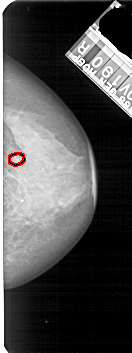

FILE: A_1683_1.RIGHT_MLO.OVERLAY

TOTAL_ABNORMALITIES 1

ABNORMALITY 1

LESION_TYPE MASS SHAPE OVAL MARGINS OBSCURED

ASSESSMENT 3

SUBTLETY 3

PATHOLOGY BENIGN

TOTAL_OUTLINES 1

BOUNDARY